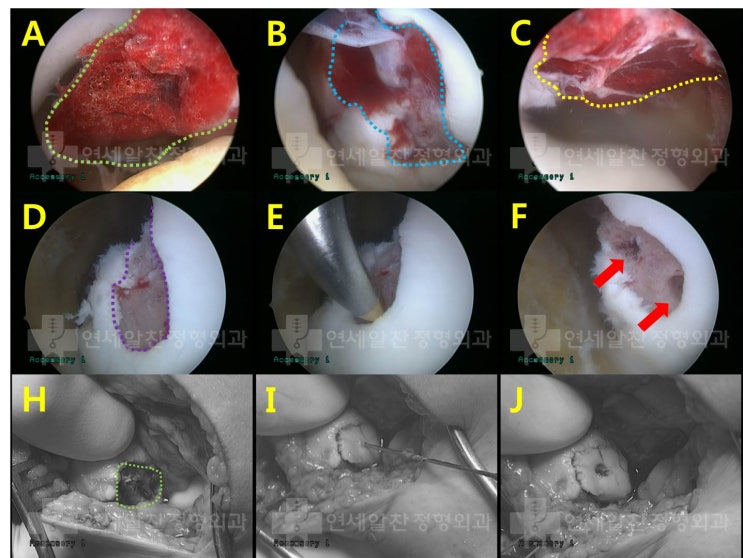

극상근 점액낭측 파열에서 이중교량형 봉합법을 이용한 수술의 결과

58세 여자환자로 3개월전 일하는 도중 발생한 어깨 통증을 주소로 본원으로 내원하였다. 타원에서 주사치료...